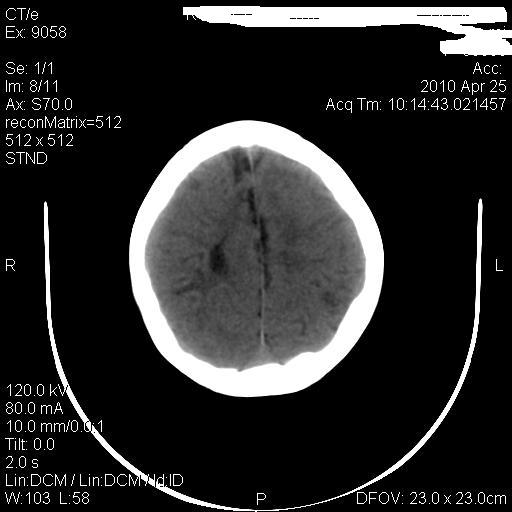

标题: PED3218:3岁女孩,曾有外伤史。未提供前片 [打印本页]

标题: PED3218:3岁女孩,曾有外伤史。未提供前片

发育略有障碍。欢迎大家发言。谢谢!

考虑右侧额顶叶脑软化灶并脑穿通畸形。

考虑:1)右侧额顶叶脑软化灶并脑穿通畸形。2)胼胝体发育不良。

支持考虑:1)右侧额顶叶脑软化灶并脑穿通畸形。2)胼胝体发育不良。

1)右侧额顶叶脑软化灶。2)胼胝体发育不良?

考虑右侧额顶叶软化灶并脑穿通畸形,胼胝体发育不全。

还有脑室周围白质软化症